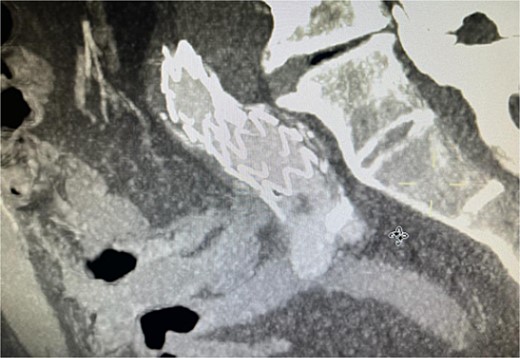

Despite these interventions, the patient experienced further episodes of acute limb ischemia (Fig. 4), leading to thrombolytic therapy a month later. This recurrence prompted a reevaluation of the treatment strategy. We considered extending the graft limb, which would involve sacrificing the hypogastric artery, or using an iliac artery extension with an iliac side branch. We ultimately chose the latter and implanted an E-iliac stent graft (Jotec ISB system) (Fig. 5a and b). Preservation of the hypogastric artery was prioritized, although extending into the external iliac artery would have been a viable alternative. However, the multidisciplinary team decided the preservation of the hypogastric artery would be more appropriate in this patient. The patient was discharged without anticoagulants.

Coronal view of CTA scan showing right femoral artery embolic obstruction